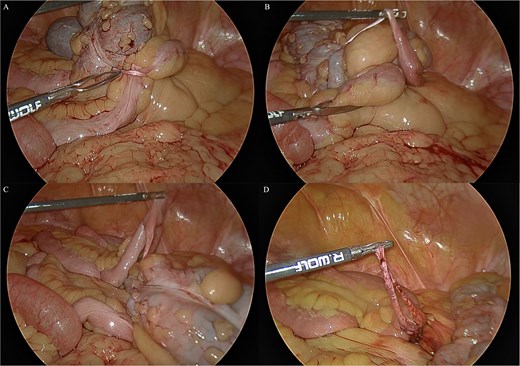

We report the case of a 71-year-old female who presented with a long history of abdominal pain and cramps since childhood. These symptoms had increased and been associated with bloating since a recent bout of uncomplicated sigmoid diverticulitis which was managed conservatively. She had recently had a colonoscopy which had failed to identify any abnormality. A computed tomography (CT) scan showed a distended caecum and suggested a degree of stenosis in the proximal ascending colon (Fig. 1). Her surgical history included an upper midline laparotomy extending to the umbilicus for an open cholecystectomy and an abdominoplasty.

Computed tomography imaging of the patient pre-operatively. (A) The structure suspected to be the band partially obstructing the caecum is indicated by the arrow. (B) The distension of the caecum prior to the obstructing band is demonstrated.